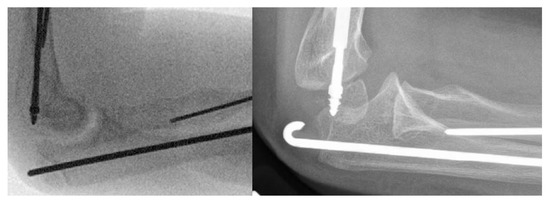

The indication for surgery in all children was deformity with recurrent fracture and loss of motion interfering with function (Figure 1). Surgical treatment of the forearm bones was discussed with families when the children were experiencing multiple radius and/or ulna fractures that resulted in bowing of the forearm that resulted in difficulties with function. All surgeries were performed by the senior author. Forty-eight total bony procedures on 18 patients were performed with 9 patients having only one forearm corrected and 9 having both forearms corrected. In total, 29 total procedures were performed on the right (14 forearms) and 19 total procedures on the left (13 forearms). Fourteen patients are right-hand dominant, 1 is left-hand dominant, and 3 do not have hand dominance recorded in the chart. Bilateral forearm surgery was performed in separate operative trips for all except one patient whose mother requested that we treat both forearms in the same operative setting. If there were recent fractures, we attempted to percutaneously pass a k-wire in the radius or ulna as we manually corrected the deformity. If this was deemed unsafe, or if an osteotomy was needed to correct the deformity, we opened at the apex of the deformity and attempted to perform one osteotomy. We routinely performed this with a rongeur, passing a separate wire into the next segment before passing the wire across the osteotomy site. If the deformity could not be corrected fully we performed a second osteotomy. The ulnar wire was placed across the olecranon apophysis to protect the entire ulna down to the distal ulnar physis. The radial wire was placed through the radial styloid across the distal radial physis up to the proximal radial physis to protect the entire radius. The radius was typically approached through the anterior volar approach, with exceptions when dorsal or radial approaches were performed depending on the apex and severity of the radial bow. When the radius has significant bowing present, it was often subcutaneous, and the approach can be safer and more direct to approach it in a non-standard direct manner. Figure 2 shows typical preoperative deformity and postoperative healed osteotomies over 5 years. Post operatively patients were placed into a sugar tong splint for 4 weeks after surgery. Postoperative X-rays were performed at 4 weeks, and patients were then transitioned to a removable splint for an additional 3–4 weeks.

Figure 2. (a,b) A 3.5-year-old male with Type III OI. Note significant radius and ulnar bowing and immediate postoperative deformity correction. 2 (c,d) With multi-level osteotomies and rod placement. (e,f) Healed osteotomies at 3 months post-op. (g,h) Two years later, at age 5.5, you can see how much the patient has grown and a fracture at the tip of the ulnar wire. (i,j) Immediate post-op after revision of the radial wire and fixation of the ulna with a new wire. (k,l) Most recent follow up X-ray at 9 years of age.